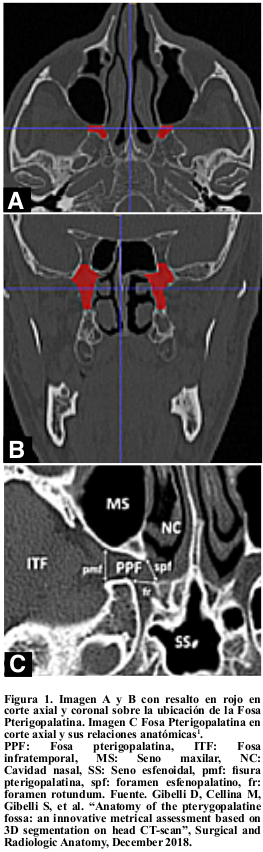

La Fosa Pterigopalatina (FPP) es un área anatómica compleja de gran importancia, que puede presentar patología tumoral, de tipo benigna o maligna y que en múltiples ocasiones amerita resolución quirúrgica. Desde el punto de vista anatómico la altura promedio es de 24,1 ± 3,5 mm en hombres y de 22,8 ± 3,4 mm en mujeres, con un volumen de 0,930 ± 0,181 cm3 en hombres y 0,817 ± 0,157 cm3 en mujeres (Figura 1)1.

1. Gibelli D, Cellina M, Gibelli S, et al. “Anatomy of the pterygopalatine fossa: an innovative metrical assessment based on 3D segmentation on head CT-scan”, Surgical and Radiologic Anatomy, December 2018. Available from:https://link.springer.com/article/10.1007/s00276-018-2153-7?shared-article-renderer